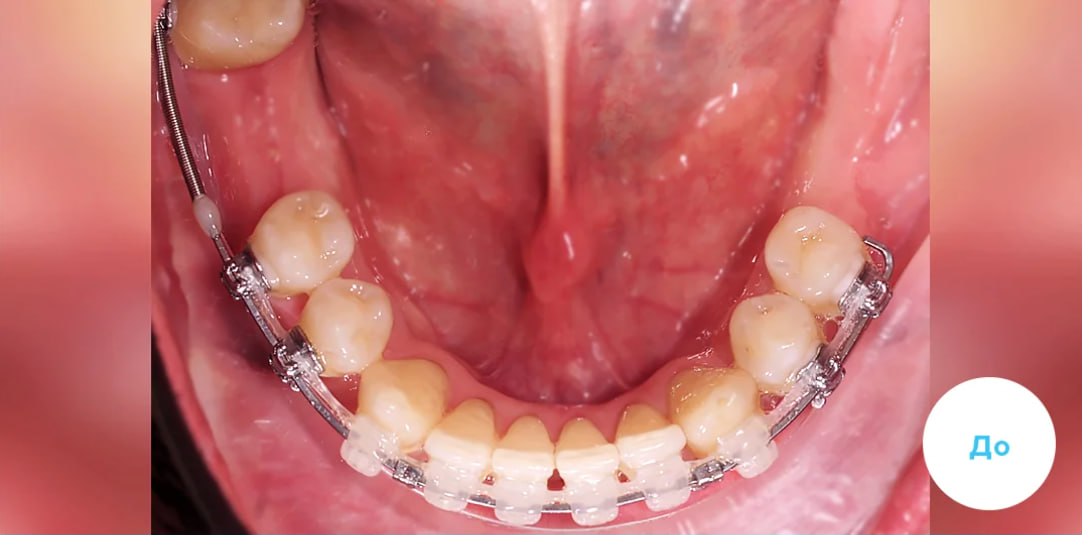

Результаты лечения